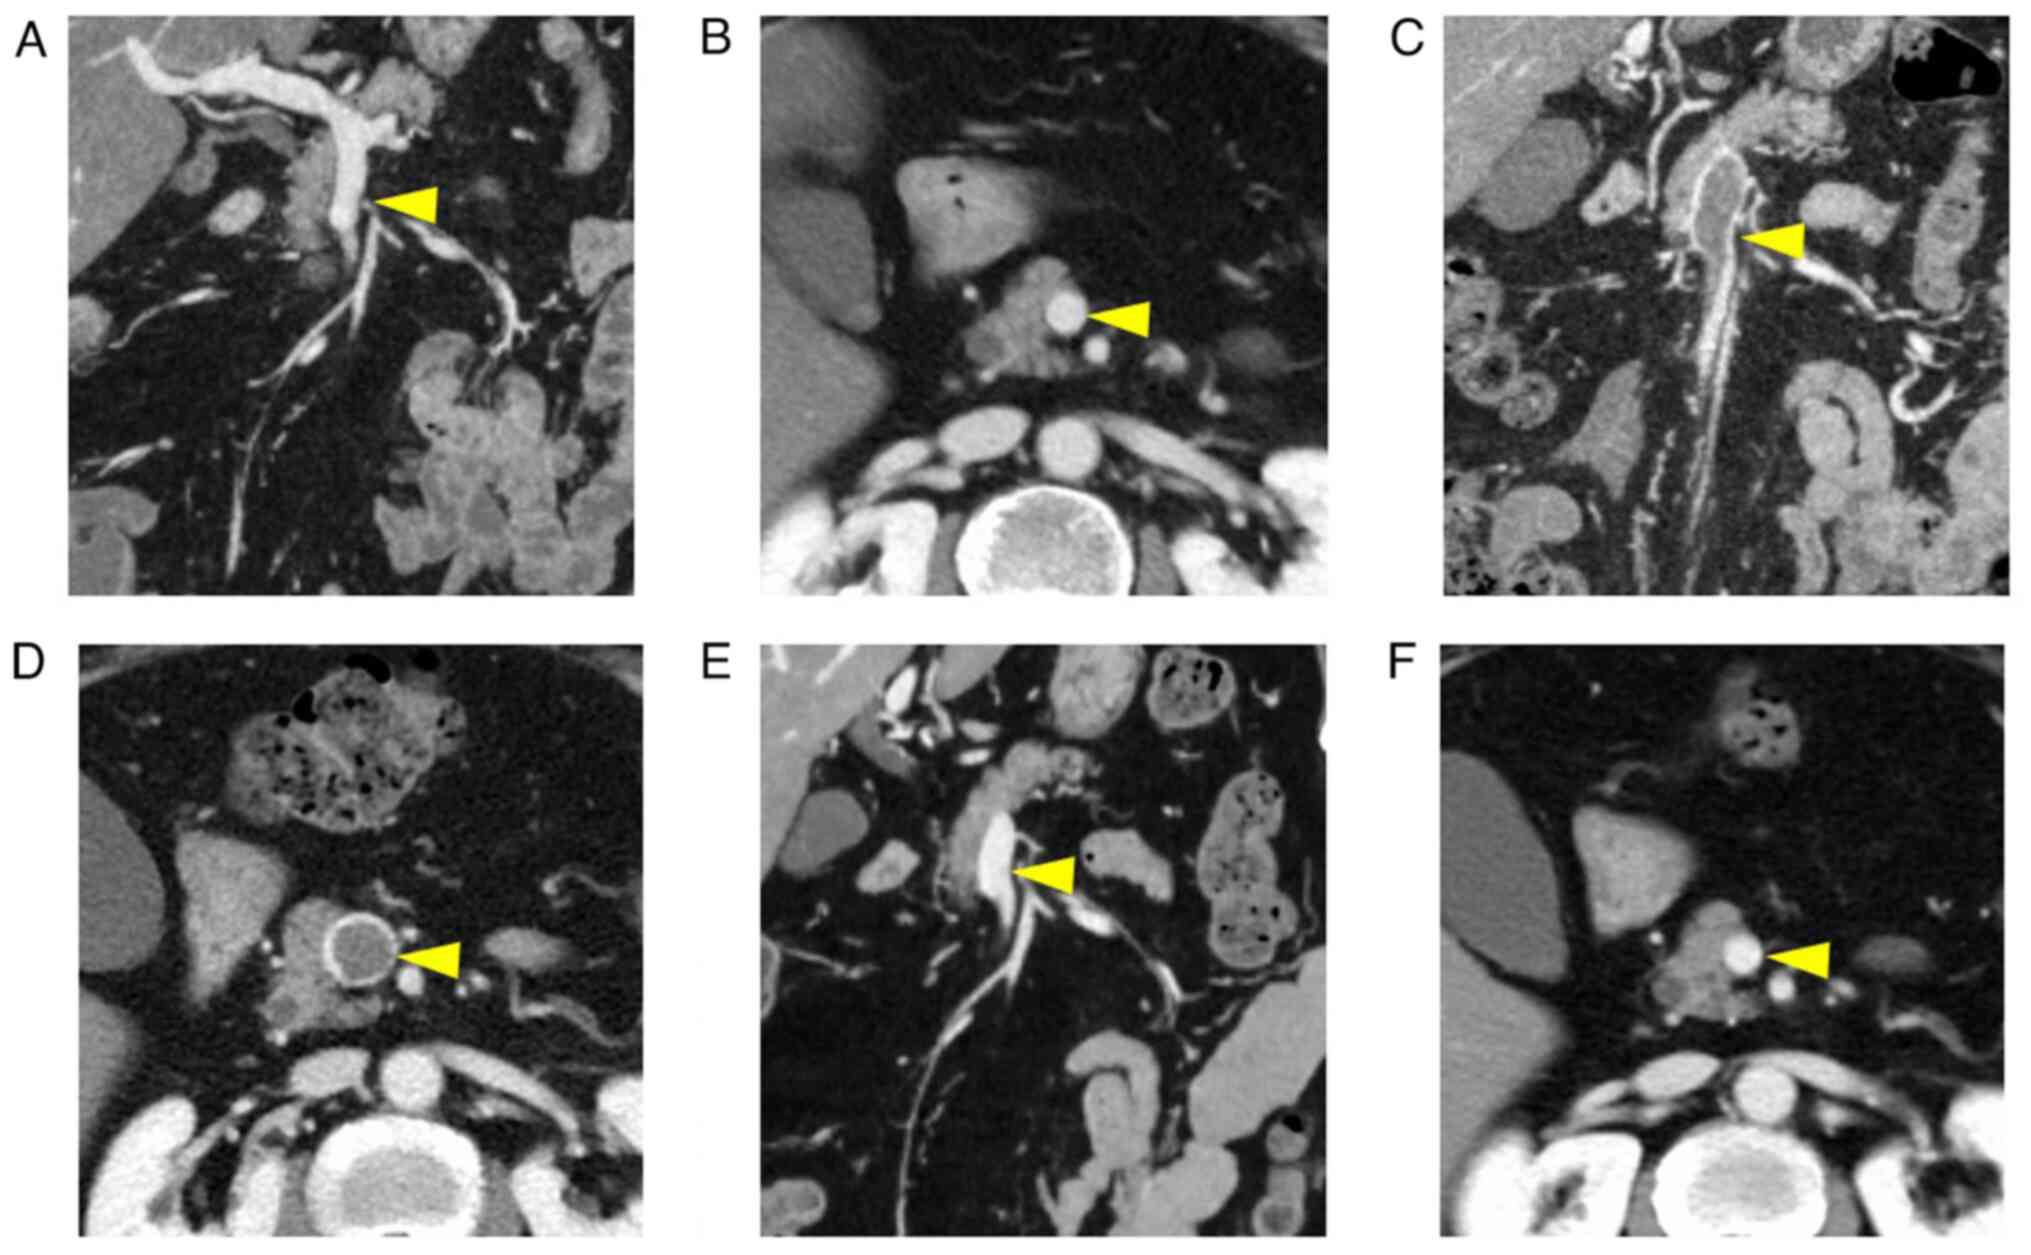

After completing chemotherapy, contrast-enhanced CT was performed in December 2020 to detect recurrence. Although no recurrence was observed, a thrombus completely occupying the SMV lumen was observed (Fig. 2A-F). Preoperative contrast-enhanced CT showed no thrombi. The patient had no abdominal symptoms after the chemotherapy. Blood tests revealed no liver dysfunction or coagulation abnormalities. D-dimer levels were 6.0 µg/ml, anti-cardiolipin antibody was negative, protein C level was 57% and protein S level was 140%. No abnormalities were evident in anti-cardiolipin antibody or protein C or S activity. Furthermore, no venous thrombus could be detected by lower limb venous ultrasonography, and no pulmonary artery thrombosis was observed on contrast-enhanced CT. Based on these findings, the patient was diagnosed with SMV thrombosis. Since no abdominal symptoms or obvious intestinal ischemia could be detected on CT, conservative treatment with anticoagulants was decided. Treatment with oral edoxaban (30 mg/day) was initiated, following which D-dimer levels normalized after 1 month. Subsequently, 6 months later, a follow-up examination revealed complete resolution of the thrombus and no recurrence of colorectal cancer in June 2021. Therefore, edoxaban treatment was discontinued (Fig. 3). No hemorrhagic events were observed during this treatment period. Subsequent follow-up is presently being conducted in an outpatient clinic to monitor recurrence and thrombus formation, and to date, no thrombus or cancer recurrence has been noted.

Figure 2

Contrast-enhanced CT images during the clinical course. (A and B) Preoperative CT showing no thrombus in the SMV. (C and D) CT images 6 months postoperatively showing that the lumen of the SMV is occupied by a thrombus. (E and F) The blood clot disappeared 6 months after taking edoxaban. Yellow arrowheads indicate the SMV. SMV, superior mesenteric vein.